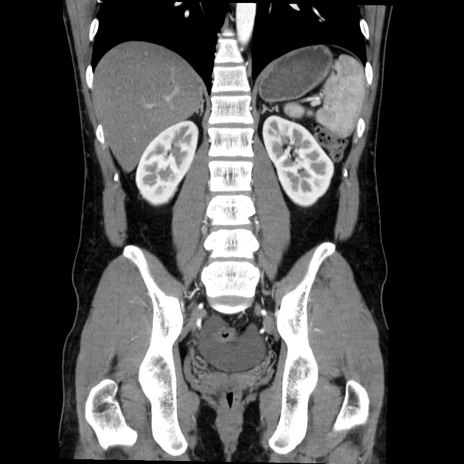

症例36(冠状断像)

【症例】20歳代 男性

【主訴】心窩部痛

【現病歴】今朝より上腹部痛あり。一旦軽快していたが再度出現したため救急要請。昨日夕に白身の魚を含む刺身を食べた。

【身体所見】BP 136/89mmHg、HR 74/min、BT 37.0℃、腹部:膨満、軟、心窩部に圧痛あり。反跳痛なし、筋性防御なし、腸雑音やや亢進あり。

【データ】WBC 17700、CRP 0.48